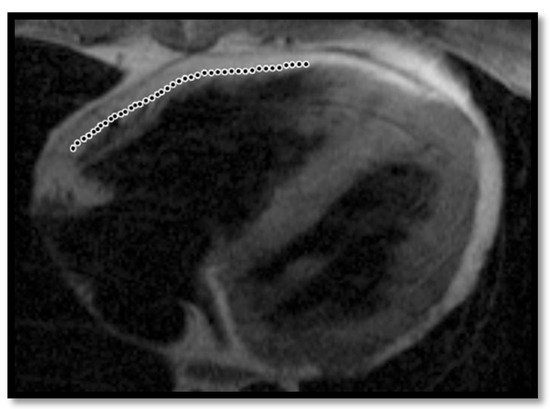

- Thinning of the RV wallThis is a component that was not included in the Task Force Criteria for the diagnosis of ARVC [12,45]. This is because the reports of different authors were not consistent with regards to the thinning or thickening of the ventricular wall. Therefore, thinning of the wall is considered pathological only when associated with contraction abnormalities at the same level [48] (Figure 6).